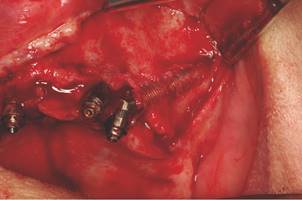

Loss of the zygomatic fixation may occur as observed in conventional implants. The zygomatic fixation presents few areas of bone contact along the entire fixation, restricting to some millimeters in the alveolar region and zygomatic bone implantation site. Therefore, it should be found the maximum bone contact between the implant and the zygomatic process of the maxilla. The adoption of techniques of externalization and use of maxillary zygomatic process may provide greater contact area. However, both the classical technique and the externalization may present advantages and disadvantages. The classical technique protects more the fixation, reduces the bone contact area and predisposes occurrence of maxillary sinus complications. The exteriorization presents greater technical facility and greater anchorage, therefore it may result an important periimplant involvement, buccal recessions and difficult control of oral hygiene. In addition, the extensive bone destruction followed the loss of fixation should be considered (Figs. 1 and 2). It is important to consider that the loss of osseointegration in alveolar portion (in the conventional technique) does not mean loss of implant, except when it is associated in a rotational movement and painful symptoms. However, when a buccosinusal communication is established, the implant must be removed, even if it was osseointegrated in the zygomatic bone.